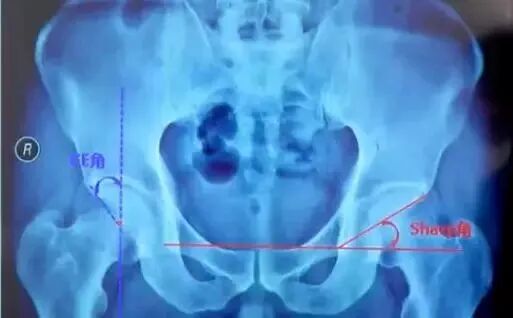

中心边缘角(CE角):

髋臼外上缘到股骨头中心连线与垂线所成之角,正常20°~30°,DDH患者此角变小,反应股骨头旋转中心移位程度,小于20°提示先天性髋臼发育不良。

Sharp角:

在骨盆正位片上,双侧泪滴下缘连线与泪滴下缘至髋臼上缘连线的夹角,正常值为33°~38°,此角大于40°提示髋臼发育不良。

髋臼指数:

成年人则为髋臼外上缘到髋臼窝中心连线与水平线夹角。髋关节结构和发育状况的一个重要判断指标。正常髋臼指数为20°~25°,大于25为髋臼发育不良。